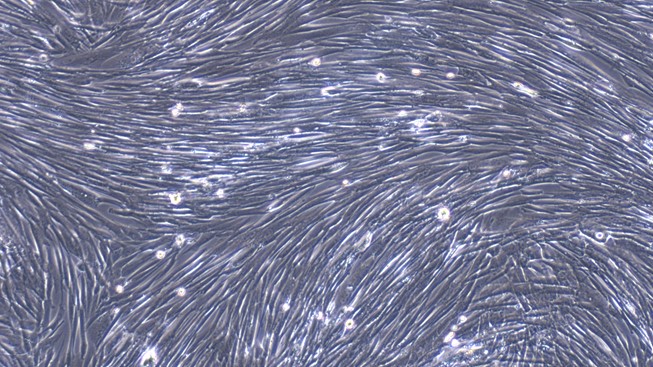

Polyclonal Antibody to Fibroblast Activation Protein Alpha (FAPa)

PAC469Mu02 | Mus musculus (Mouse)